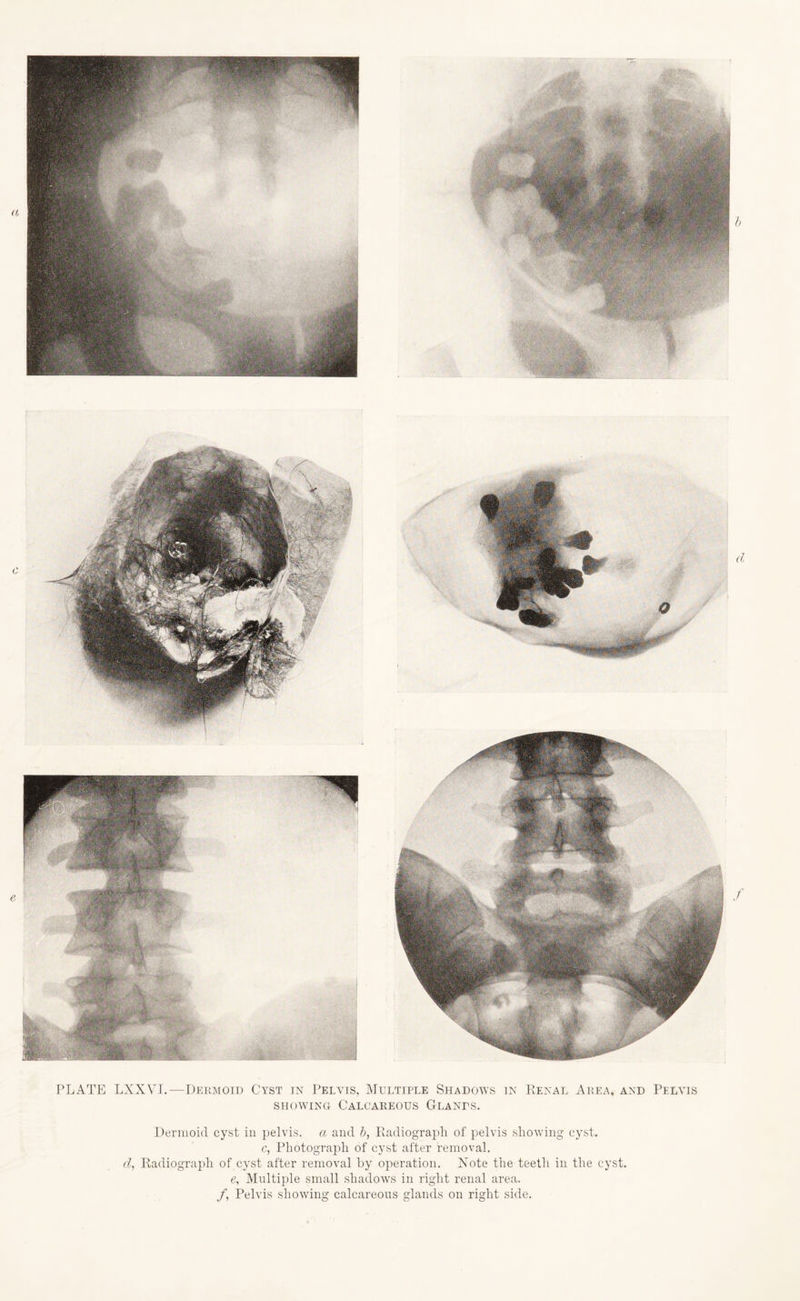

Radiography and radio-therapeutics / by Robert Knox.

505/544 page 381